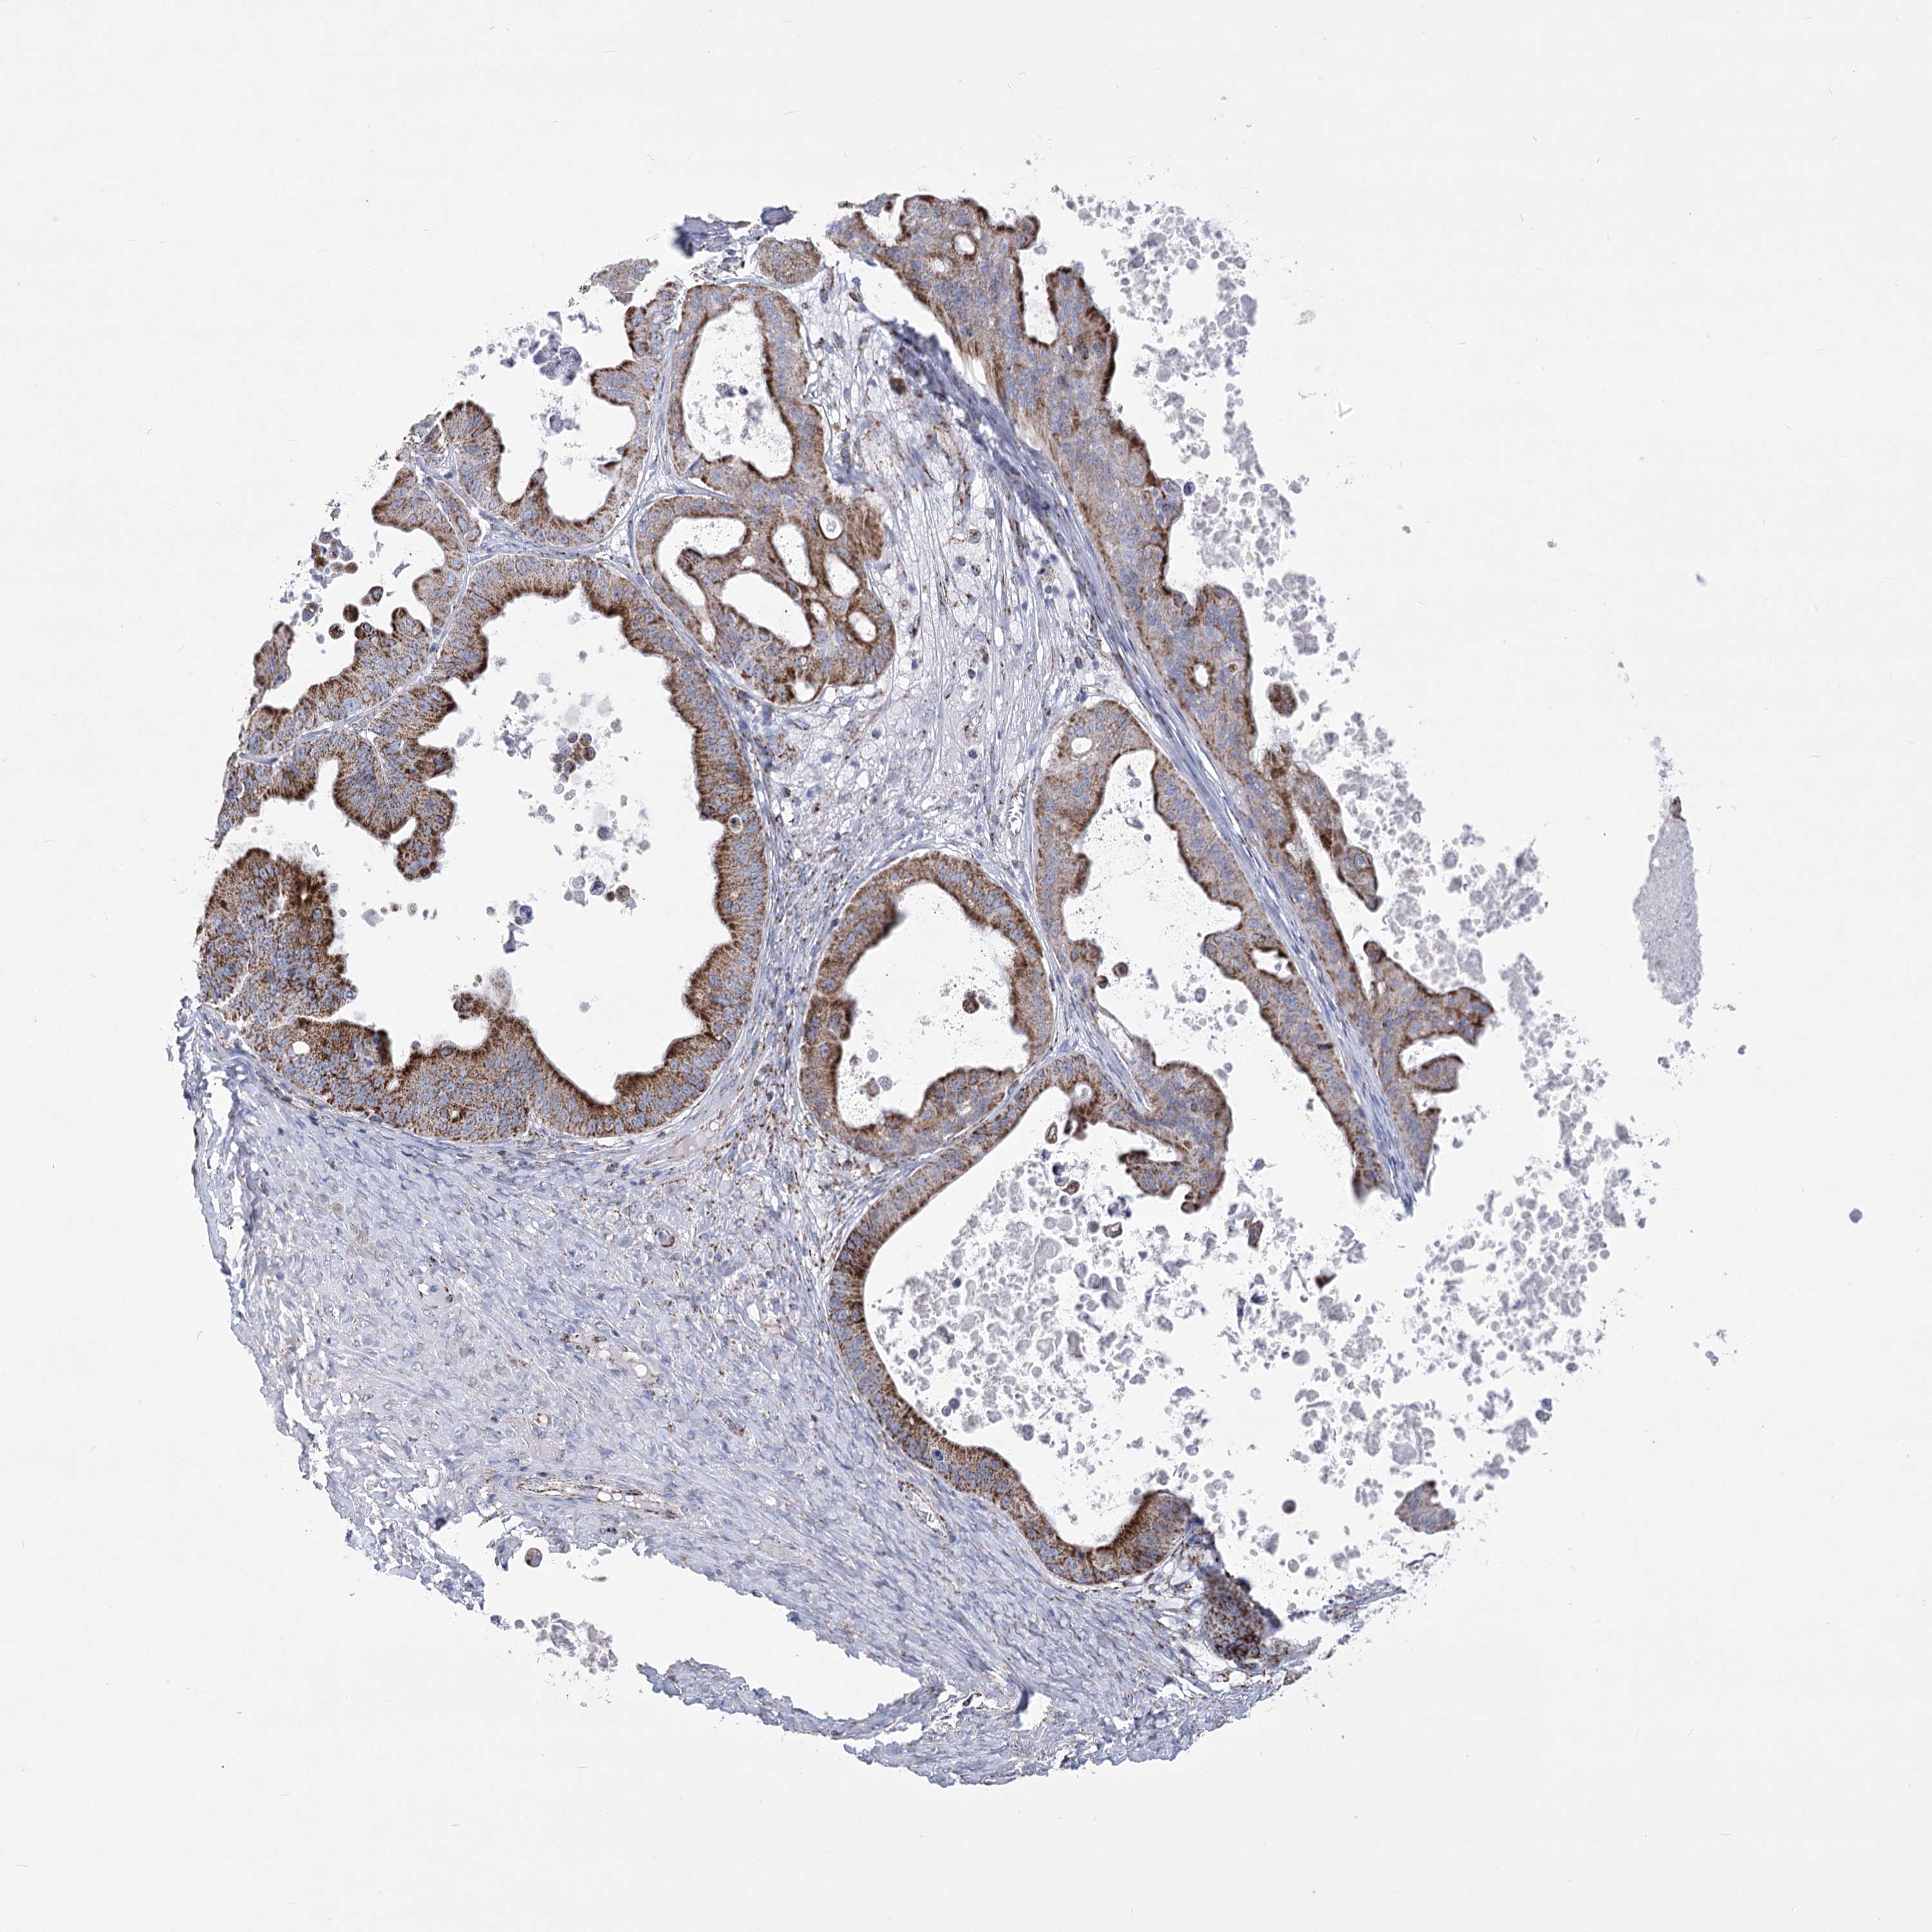

OVARIAN CANCER - Protein expressioni

A mouse-over function shows sample information and annotation data. Click on an image to view it in a full screen mode. Samples can be filtered based on level of antibody staining by selecting one or several of the following categories: high, medium, low and not detected. The assay and annotation is described here.

Note that samples used for immunohistochemistry by the Human Protein Atlas do not correspond to samples in the TCGA dataset.

Antibody stainingi

Antibody staining in the annotated cell types in the current human tissue is reported as not detected, low, medium, or high, based on conventional immunohistochemistry profiling in selected tissues. This score is based on the combination of the staining intensity and fraction of stained cells.

Each image is clickable and will lead to virtual microscopy that enables deeper exploration of all samples and also displays staining intensity scores, fraction scores and subcellular localization as well as patient and tissue information for each sample.

Antibody HPA036744

Antibody HPA036745

Antibody CAB033794

Cystadenocarcinoma, serous, NOS

Carcinoma, endometroid

Cystadenocarcinoma, mucinous, NOS

Carcinoma, NOS